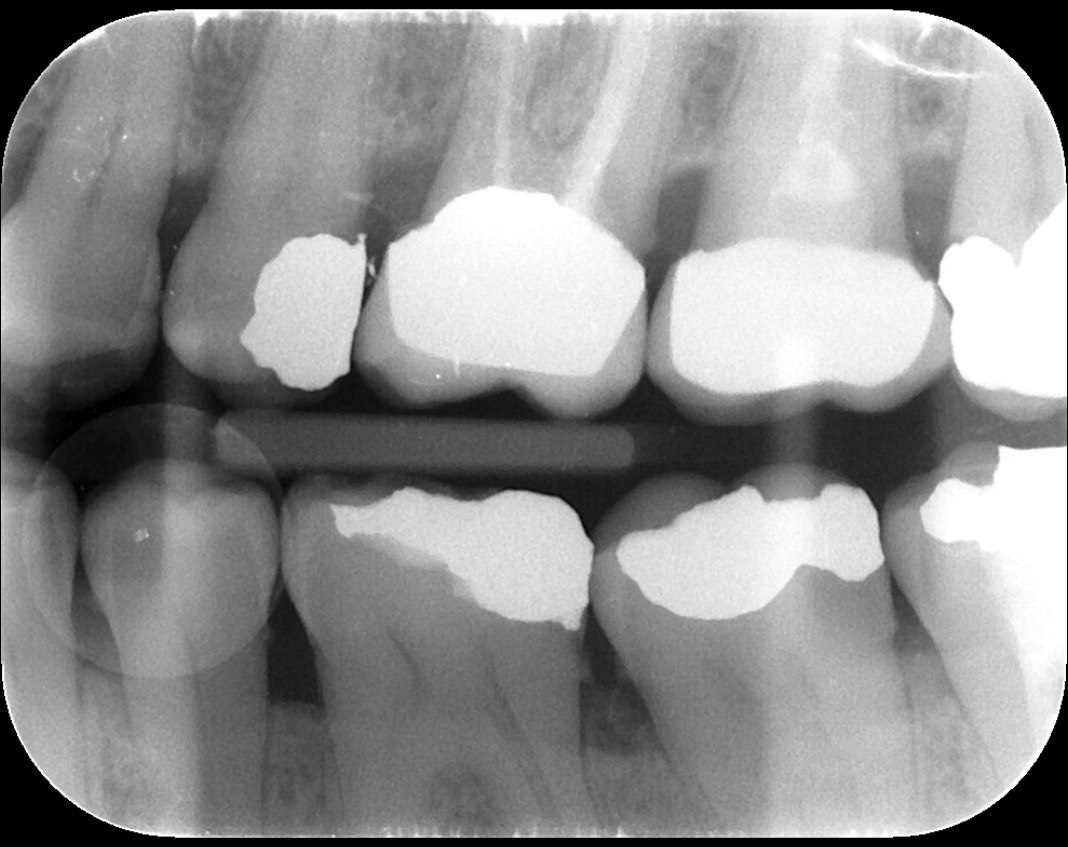

Question 1: What materials cannot be seen in the print of the X ray?

Question2: Which surface shows overhang?

Question 3: Which option is not evident on the print of the X ray?

Question 4: Which options cannot be seen in the print of the X ray?

Question 5: What options cannot be selected for tooth # 4.6?

Question 6: What options cannot be seen in the print of the X ray?

Question 7: What option cannot be identified on the print of the X ray?

Question 8: What condition can be seen in the X ray?

Question 9: Which option cannot be seen in the lower jaw?

Question 10: Which option can be selected for the following X ray?

Question 11: Which materials cannot be seen in the print of the X ray?

Question 12: What option cannot be selected for the following X ray?

Question 13: What option cannot be selected for the following X ray?

Question 14: Which surface shows overhang restoration?

Question 15: Which surface shows overhang in the restoration?

Question 16: Which surface shows overhang?

Question 17: Which surface shows overhang?

Question 18: Which surface shows overhang?

Question 19: Which option can be chosen for the tooth # 3.6?

Question 20: which tooth shows defective resotration?

Question 21: What option is can be selected for distal tooth # 4.6?

Question 22: Which surface shows defective restoration?

Question 23: Which surface shows overhang?

Question 24: Which surface shows defective restoration?

Question 25: Which surface shows open margin?